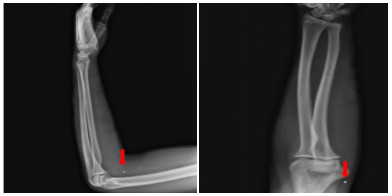

患者入院后无胸闷气促等不适主诉。入科查体:体温36.5 ℃,脉搏86次/min,呼吸频率16次/min,血压106/54 mmHg(1 mmHg=0.133 kPa),指尖氧饱和度99%~100%(未吸氧情况下),神清,瞳孔等大等圆,对光反射可,双肺呼吸音清,无明显干湿啰音,听诊心脏,律齐,无病理性杂音,左侧前臂近端及远端各一创面包扎,敷料干燥,未见明显渗出,左上肢肌力无法配合(考虑臂丛阻滞麻醉未完全恢复),余四肢肌力肌张力感觉无明显异常。立即完善相关检查(图 3、4),通过X线以及CT定位异物,超声评估异物在心脏中的活动情况及与心脏搏动时与瓣膜以及周围组织结构关系,可见异物在心脏内较固定,未影响瓣膜运动。同时血化验(动脉血气、感染指标、心肌酶谱、肌钙蛋白、D二聚体等)及心电图未见明显异常,请心胸外科会诊后建议暂予以抗炎保守对症处理。

| 图 3 外伤后第三次评估异物情况肺部CT检查图像 |